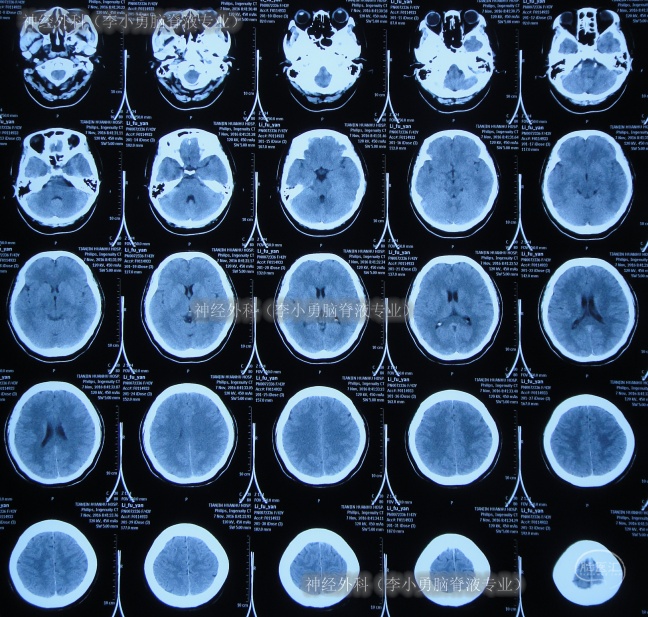

患者从2006年左右开始出现间断头痛反应,尤其在咳嗽、哭笑时头痛加重,一直保守治疗,间断头痛十余年后即2016年10月23日,头痛症状加剧实在无法忍受,就诊于天津市某区医院,查头颅CT(图-1)后怀疑是小脑扁桃体下疝,建议进一步检查。在神经外科(李小勇脑脊液专业)治疗过程和结果】

图-1:2016年10月23日头颅CT

2天后即2016年10月25日,天津市某三甲医院,查MRI(图-2)后确诊小脑扁桃体下疝。

图-2:2016年10月25日头颅MRI

由于该院床位紧张11天后即2016年11月5日,住入该院,再次查头颅MRI和CT(图-3、图-4)后计划行后颅窝减压术枕大池成形术。

图-3:2016年11月6日头颅MRI

图-4:2016年11月7日头颅CT

入院后4天即2016年11月9日,按计划进行了“后颅窝减压术枕大池成形术”。术后次日查头颅CT示未见明显异常(图-5)。

图-5:2016年11月10日头颅CT

2016年11月28日(术后20天),查查头颅CT(图-6)和脑脊液化验均示仍感染,继续抗感染后症状仍无好转。

图-6:2016年11月28日头颅CT